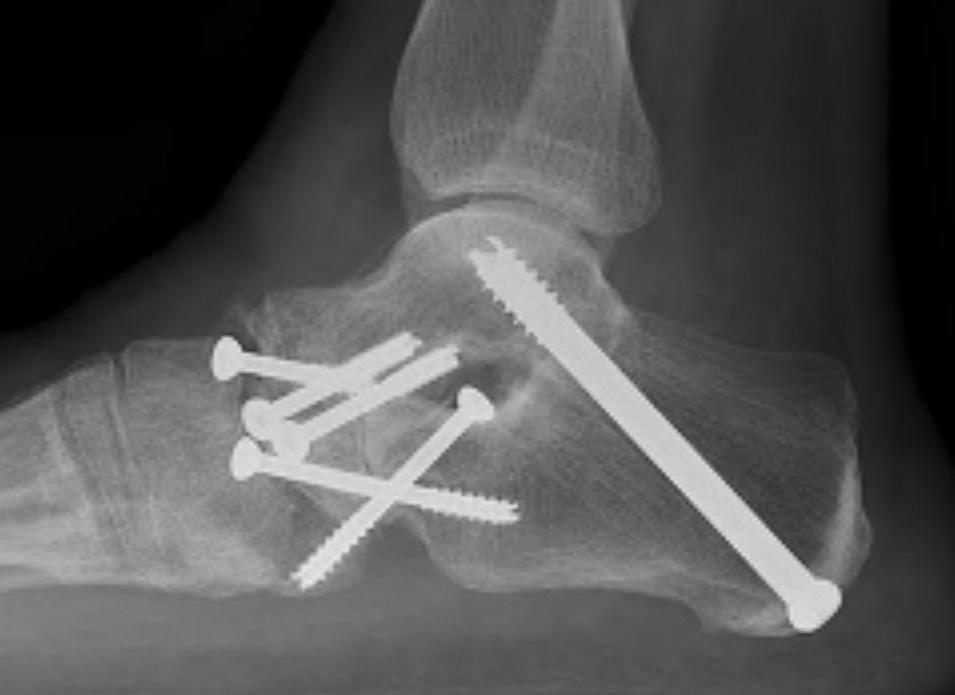

Fixation

- 6.5 mm/ 8.0 mm cannulated screw

- inferior calcaneum into body and neck of talus / talus to calcaneum

- TJN screws

- CCJ screws +/- plate

- STJ screws